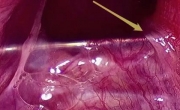

Once the peritoneal layer of the right mesocolon is opened caudad to cephalad, the ileocolic vessels are divided, followed by the right colic vessels.

This is our technique of choice; it allows to open the retromesocolic space and to mobilize the colon from its retroperitoneal attachments without excessive manipulation.

The peritoneal layer of the mesocolon is opened anterior to the mesenteric axis, along the right margin of the root of the mesentery.

This reveals the superior mesenteric vein and opens the right retroperitoneal space. The third duodenum and the head of the pancreas are the best landmarks to find the right plane.